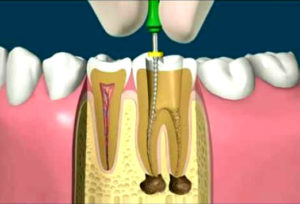

El objetivo principal y tratamiento ideal en endodoncia, es conservar la pulpa dental «nervio», o realizar procedimientos curativos en el conducto dental (tratamiento de conducto), evitando la perdida de los dientes.

El objetivo principal y tratamiento ideal en endodoncia, es conservar la pulpa dental «nervio», o realizar procedimientos curativos en el conducto dental (tratamiento de conducto), evitando la perdida de los dientes.